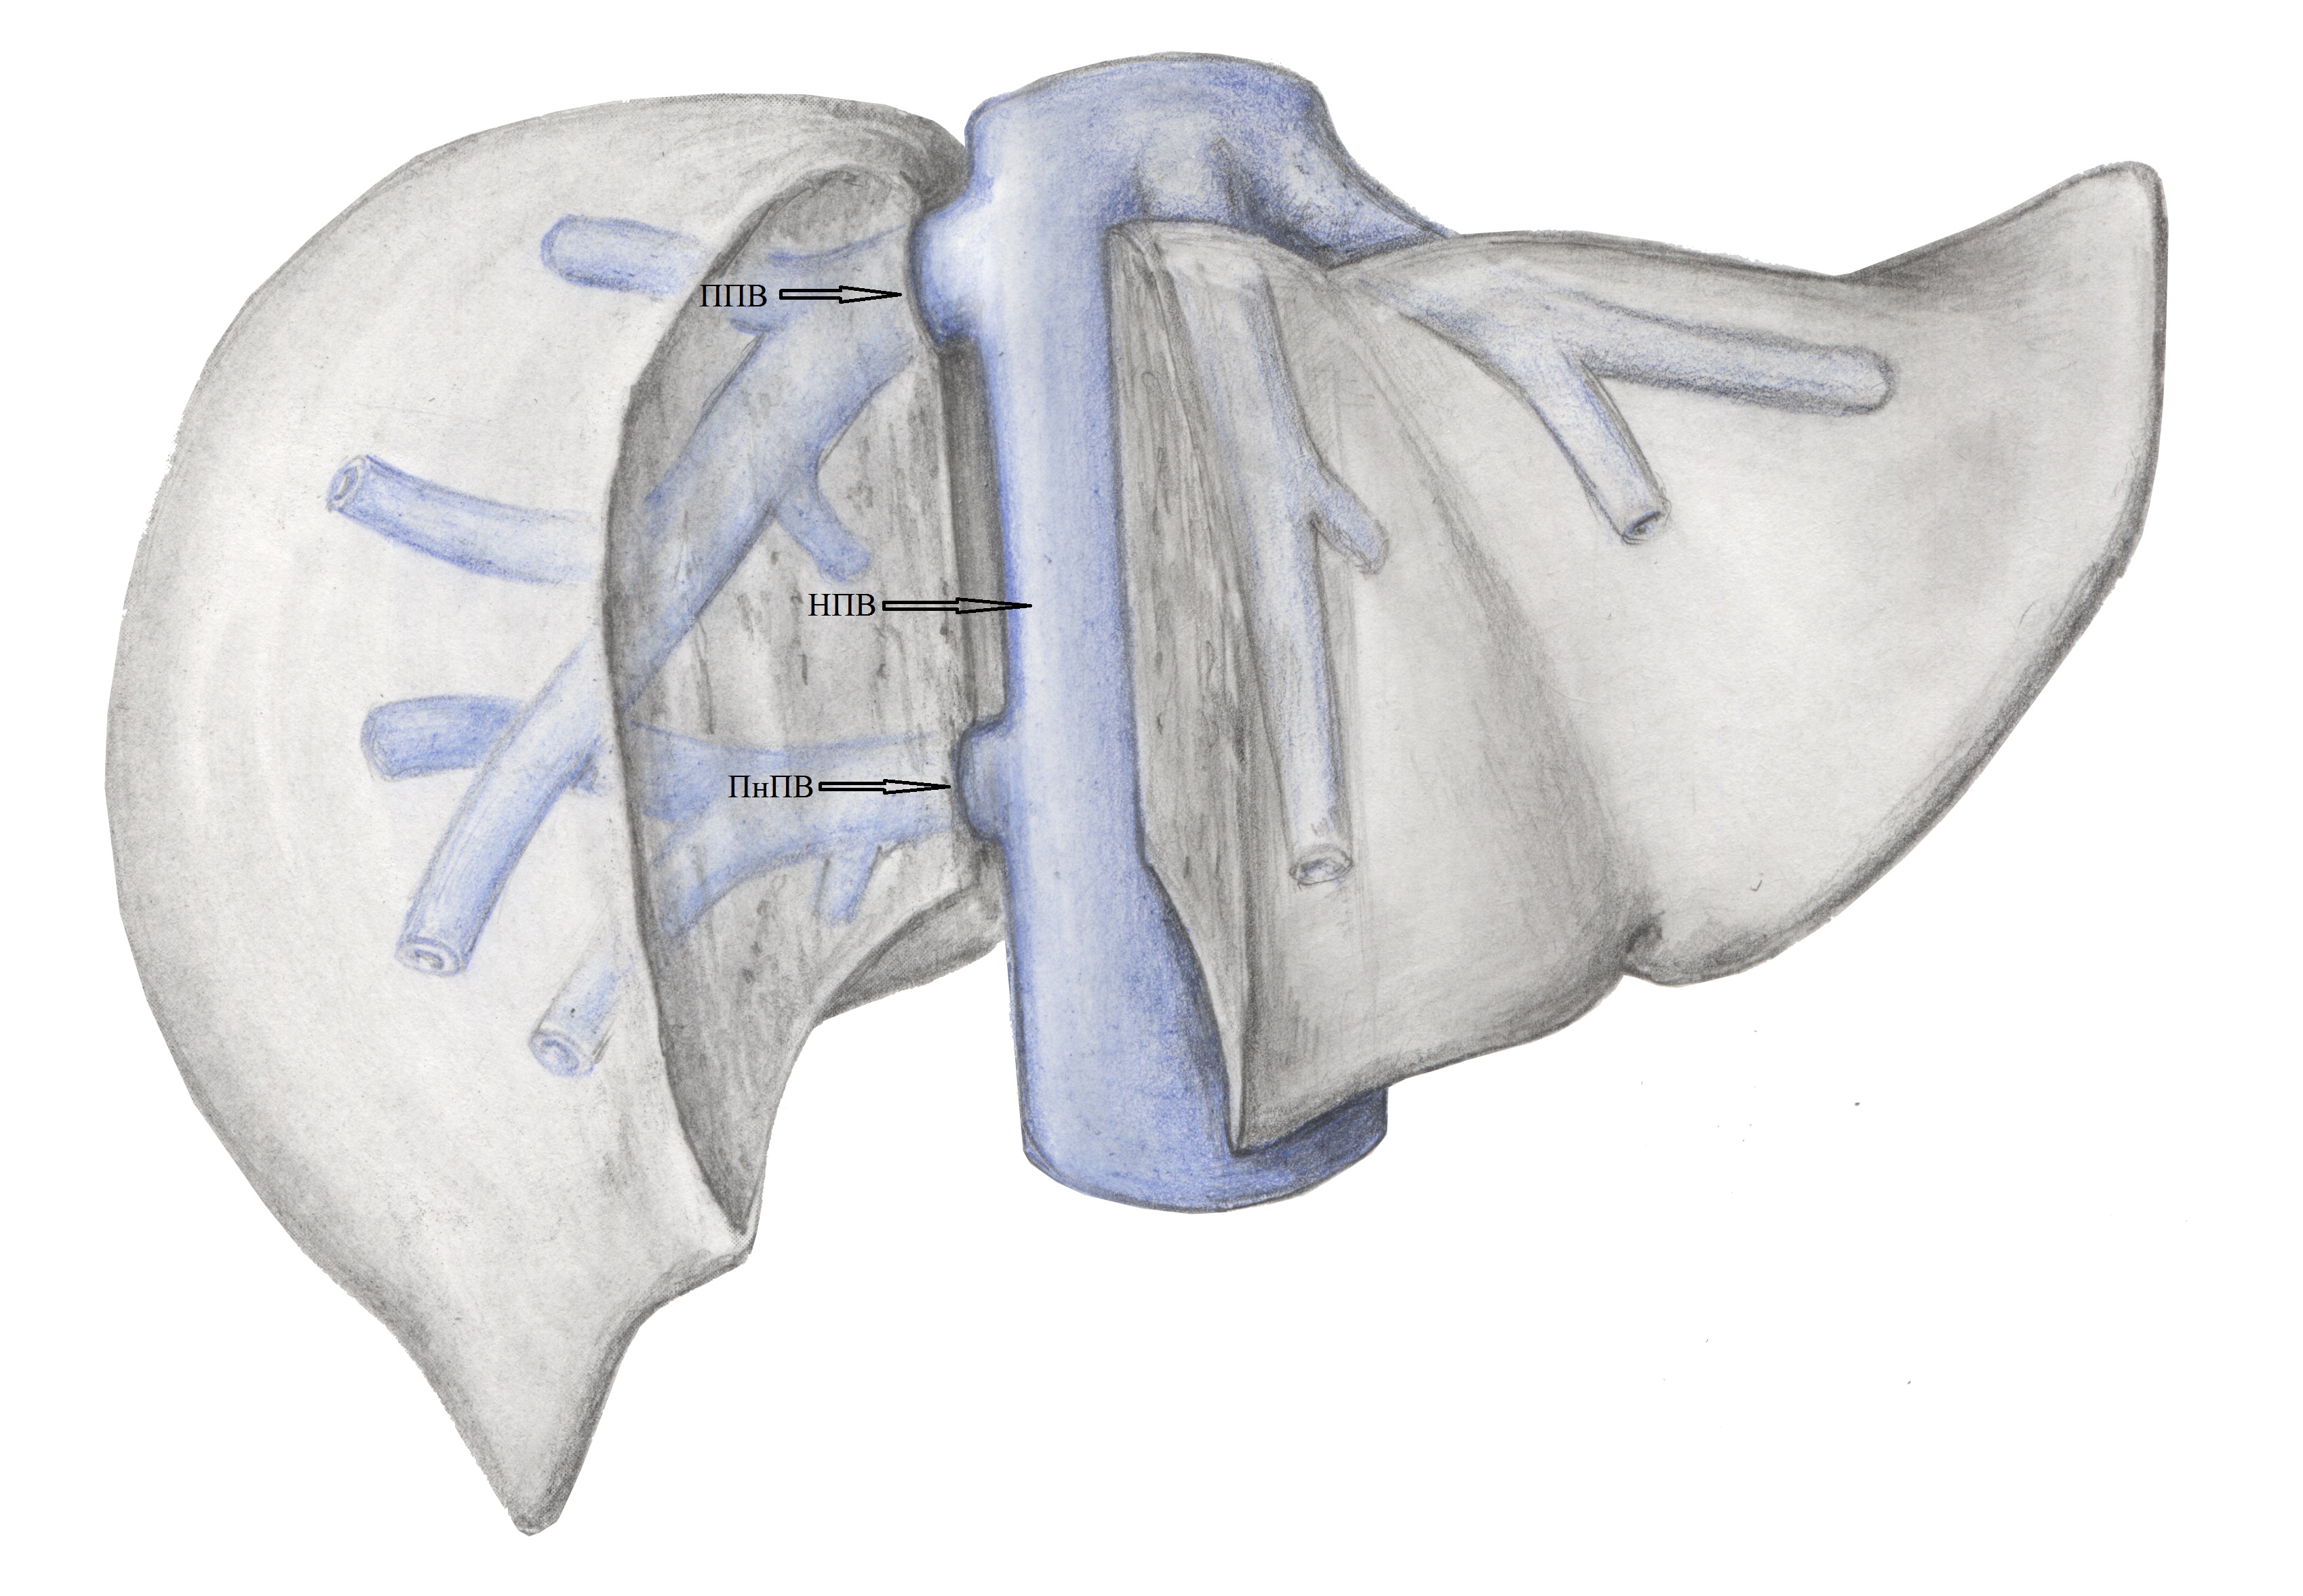

8. Тип С (схема). | |

| Тема | ||

| Тип | Исследовательские инструменты | |

Посмотреть

(1MB)

|

Метаданные ▾ | |